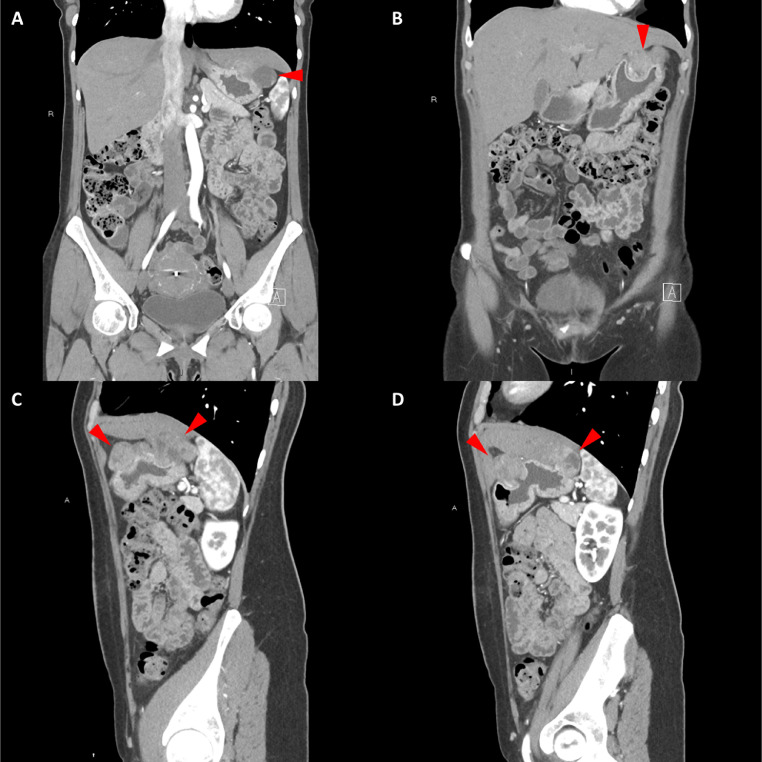

頸部增強(qiáng) CT 顯示 2 個(gè)強(qiáng)烈強(qiáng)化的腫塊。 一個(gè)位于頸部右側(cè),位于右側(cè)頸內(nèi)動脈后方的頸動脈間隙中,位于莖突內(nèi)側(cè),大小為 24 × 24 × 30 mm,頸靜脈橫向移位(圖 1A)。 第二個(gè)位于左側(cè)頸動脈間隙,在分叉處正上方展開頸外動脈和頸內(nèi)動脈,尺寸為 15 × 18 × 22 mm(圖 1B)。 影像學(xué)檢查結(jié)果與右側(cè)迷走神經(jīng)和左側(cè)頸動脈體副神經(jīng)節(jié)瘤一致,與之前的活檢結(jié)果一致。

Fig. 1

圖1:右側(cè)迷走神經(jīng)和左側(cè)頸動脈體副神經(jīng)節(jié)瘤。 (A) 軸位增強(qiáng) CT 顯示右側(cè)頸動脈間隙、右側(cè)頸內(nèi)動脈后方(白色箭頭)和莖突內(nèi)側(cè)有強(qiáng)烈強(qiáng)化的腫塊(紅色箭頭)。 (B) 軸位對比增強(qiáng) CT 顯示左頸動脈間隙有強(qiáng)烈強(qiáng)化的腫塊(紅色箭頭),向后張開頸內(nèi)動脈(紅色箭頭),向前張開頸外動脈(紅色箭頭)。 (C) 冠狀對比增強(qiáng) CT 顯示兩個(gè)增強(qiáng)腫塊(紅色箭頭)。